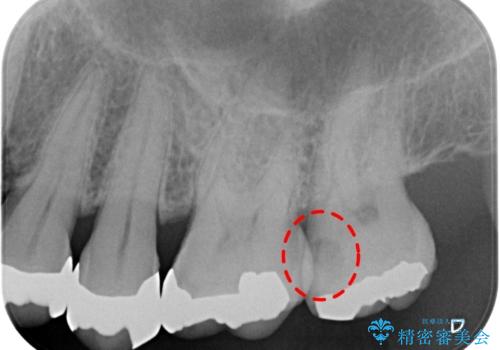

- 検査の結果左上の歯と歯の間に虫歯が発見された患者様です。

虫歯の除去後セラミックインレーでの修復処置をしていきます。

歯と歯の間は虫歯の好発部位とされています。

適合の良いインレーでの修復をすることで再発を防止します。